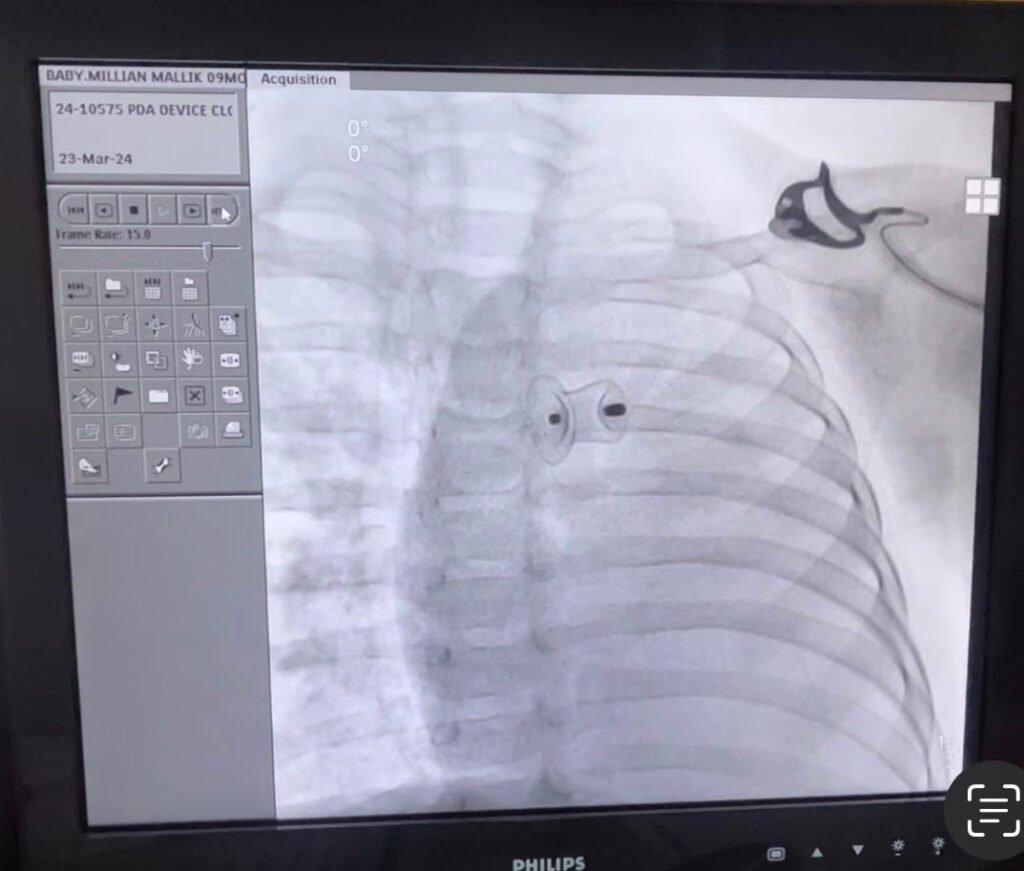

PDA + ASD

Simultaneous PDA + ASD device closure. Double device closure in single procedure. We performed a complex congenital intervention in small child who was labelled as Severe inoperable pulmonary arterial hypertension with large PDA & ASD. Thanks to entire team , Praveen & Siva garu, senior cath Technitian, Sarala sister and entire team. MVP Vizag team.